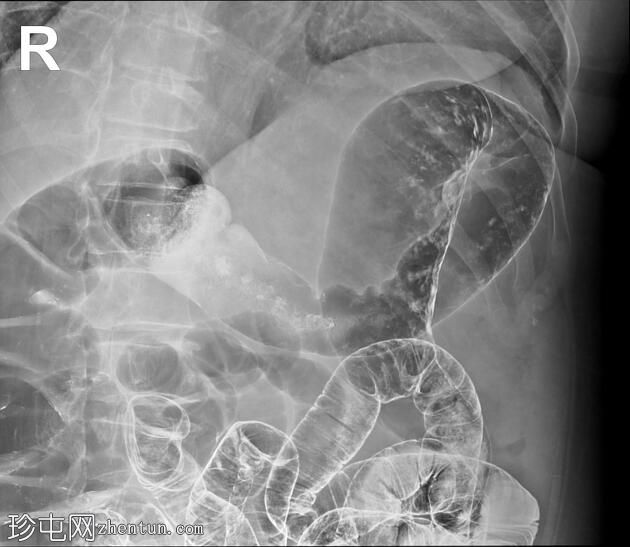

结肠异常表现包括结肠袋皱襞消失,使其外观模糊,呈铅管样改变。

其他异常表现包括降结肠和乙状结肠肠袢狭窄,以及横结肠和降结肠多处黏膜糜烂(双对比增强图像可见)。

未见肿块或瘘管形成。

升结肠外观正常,结肠袋皱襞完整。

结肠呈铅管状外观是慢性炎症性肠病(溃疡性结肠炎)的典型放射学表现。